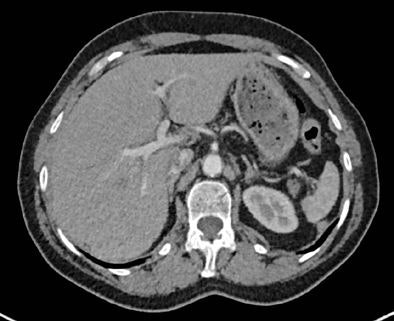

Filtered back projection (FBP) was applied to the full dose images obtained using data from both x-ray tubes, while half-dose datasets were reconstructed from only one tube-detector system, effectively halving the dose. The SAFIRE technique (set at strength 3 from a range of 1-5) was applied to the half-dose images and FBP was applied to the full-dose (two tube) images.

Noise that deteriorated image quality occurred in 24/25 (96%) of the half-dose FBP images but not in full-dose FBP and HD-raw databased iterative reconstruction datasets (p < 0.001), the authors reported. Other artifacts occurred with similar prevalence among the datasets, they said, and no significant differences were found between the three image datasets for the presence or absence of other artifacts besides noise (p > 0.05). The inter-reader agreement for image quality analysis was moderate to good (kappa = 0.579 - 0.701).

Finally, sharpness of the aortic contour was found to be significantly better for the full-dose FBP (median score 1) and half-dose SAFIRE (median score 1) versus the half-dose FBP images (median score 2, p < 0.001).